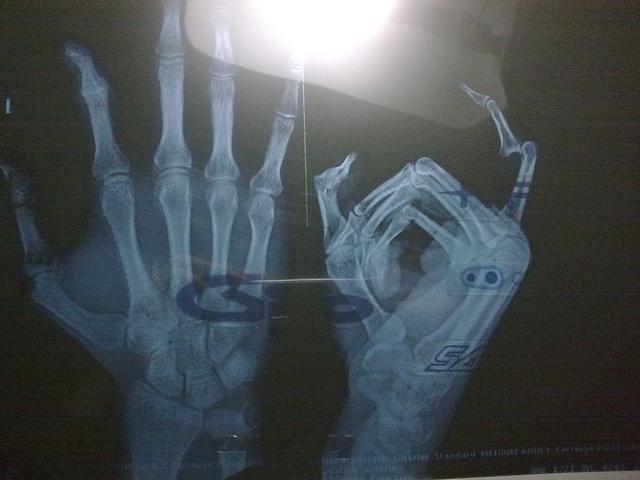

事发情况是这样的:端午节第二日,我和几个车友还有其中一个车友父母约同一起去八达岭度假,我和其中几个车友骑车到八达岭,我即将抵达八达岭的时候,汽车赶到我身边,我见机休整下,想打开后备箱放我的手套,也许当时已经很累,或是天气闷热,身体发虚,我也不知道怎么按后备箱按钮的时候,这么寸,我的左手食指像触电一样,心想这下完了,食指扭曲了,当时也没心情拍下来,怕各位车友吓到,我从前也有过相同事故,只是后来自己能复位,这次不一样了,怎么弄也回不去了,我勉强骑到度假的地方,看手指实在回不去,就托付车友的母亲开车一行赶到延庆县医院,拍片子,一看真是脱臼脱的大发了,还说其间隙有什么小骨片,医生要给我复位说要我做好心理准备,我还以为多疼呢,暗自告诉自己没事,挺住,不够他给我复位的时候也没 感觉到疼啊,难道是我麻木了,不够这次我是真吓到了,因为是人生中第一次因为受伤而进医院。

总之,这次太诡异了!!我彻底无语!! 20080211123.jpg 20080211124.jpg 20080211125.jpg 20080211126.jpg

悲剧!我已经看懂X片里的悲剧!祝早日康复!